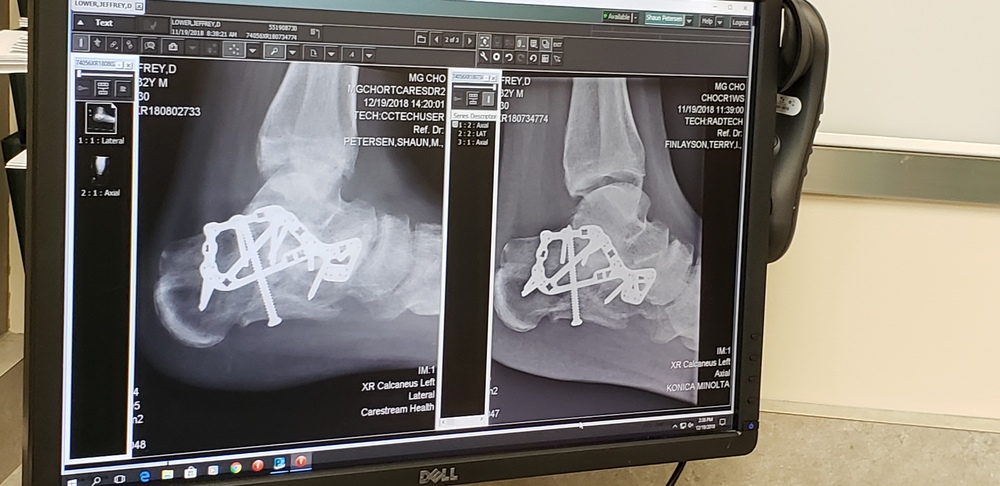

Hi Jeff ,man hope u get better soon,one question why u doc put the long screw that way in first place ,maybe he mest up the using too long siize of it...... doctors... |

pete petem75 wrote: Hi Jeff ,man hope u get better soon,one question why u doc put the long screw that way in first place ,maybe he mest up the using too long siize of it...... doctors... I think that pin was the only way to securely hold this broken portion of calcaneus back to itself. You seem skeptical about the doctors, how come buddy? |